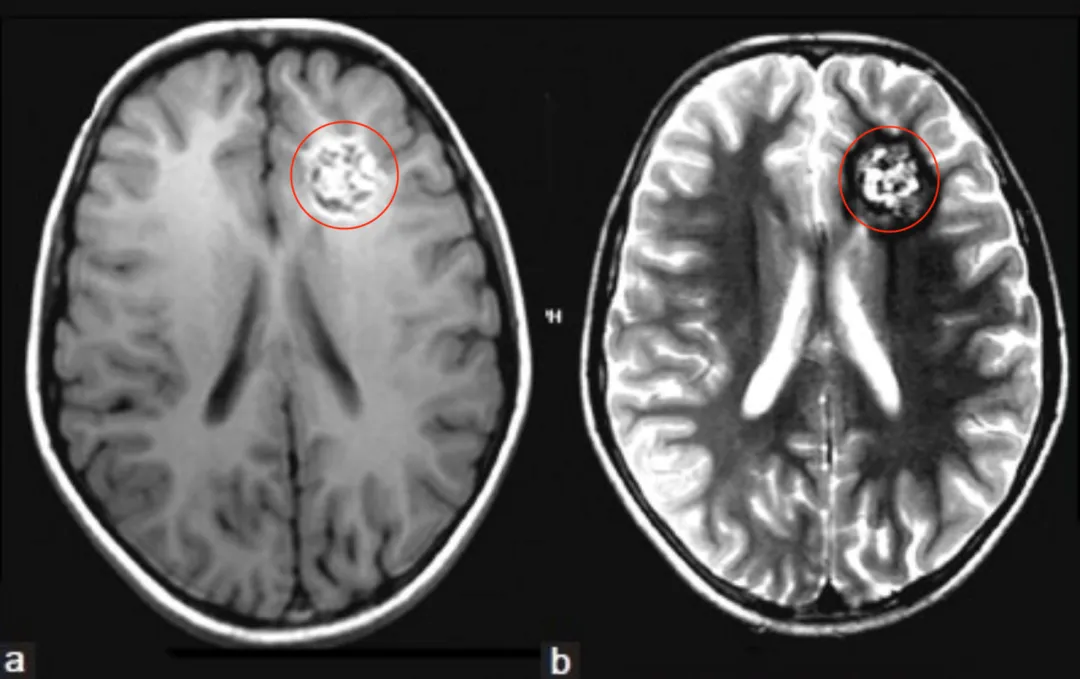

途中,她突然出现头晕症状,右眼视物开始模糊,右侧口腔和舌头也相继出现麻木感。医院的检查结果让她愣在了原地——右侧丘脑部位,发现一枚直径约5至6毫米的海绵状血管瘤。...